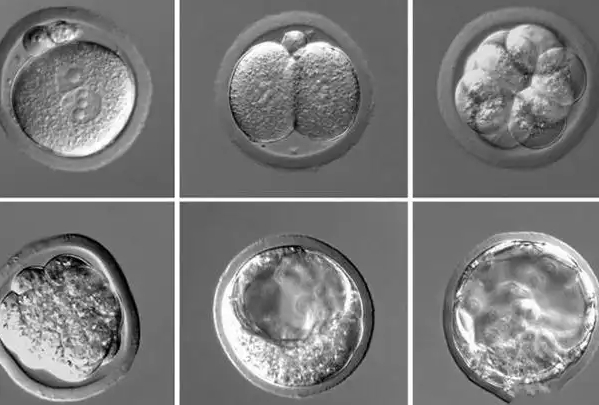

要判断 “发育缓慢” 是否异常,需先明确养囊 5 天的正常发育阶段与标准。根据囊胚评分体系(如 Gardner 评分),养囊 5 天的正常囊胚通常处于 3-5 期:3 期囊胚已形成明显囊腔,囊腔体积超过胚胎体积的一半,内细胞团(将来发育为胎儿)和滋养层细胞(将来发育为胎盘)开始分化;4 期囊胚囊腔完全充满胚胎,胚胎体积增大,透明带变薄;5 期囊胚则开始从透明带中孵化。若养囊 5 天胚胎仍处于 2 期及以下(如囊腔体积小于胚胎一半、未出现明显细胞分化),或虽达 3 期但细胞分化不清晰、细胞数量少,则可判定为发育缓慢。需注意,不同实验室的培养条件略有差异,标准可能存在细微不同,需以所在实验室的评估为准。